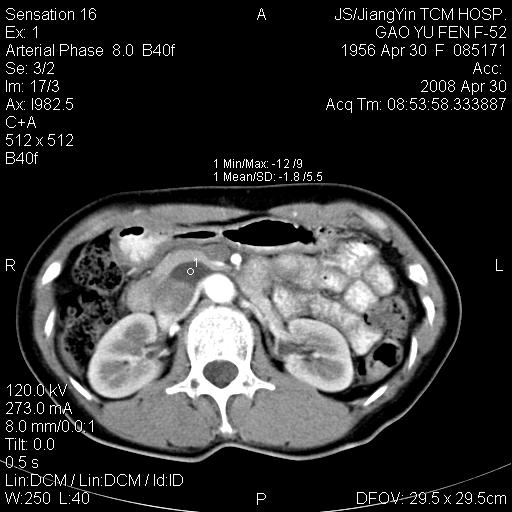

标题: CT13307:肠系膜囊肿? [打印本页]

标题: CT13307:肠系膜囊肿?

囊性淋巴管瘤可能比较大。

良性囊性占位,来源于肠系膜的可能性大

图像少,不能连续起来看,不太敢确定囊肿前方的条状结构是十二指肠水平段?如果是,那肠系膜囊肿,淋巴管瘤都有可能。

病变位于肾静脉后方,支持腹膜后占位性病变,以囊性淋巴管瘤可能性大.